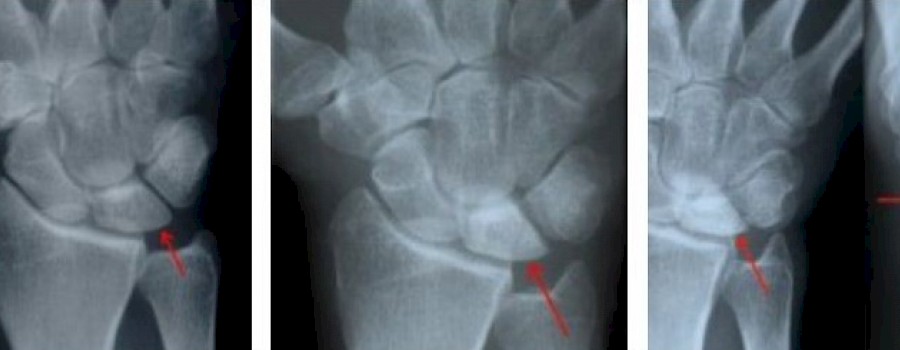

Die Lunatummalazie, auch Lunatumnekrose, Mondbeintod oder Morbus Kienböck genannt, ist eine Erkrankung, bei der es zu einem teilweisen oder vollständigem Absterben (medizinisch: Nekrose) des Os Lunatums (Mondbein, Handwurzelknochen) kommt.